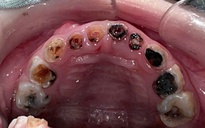

Tại Việt Nam, kết quả điều tra sức khỏe răng miệng cho thấy, hơn 90% người dân từng mắc các bệnh lý răng miệng ở các mức độ khác nhau. Những con số này nói lên thực tế: bệnh răng miệng không phải là vấn đề nhỏ của từng cá nhân, mà là một thách thức sức khỏe cộng đồng cần được quan tâm đúng mức.